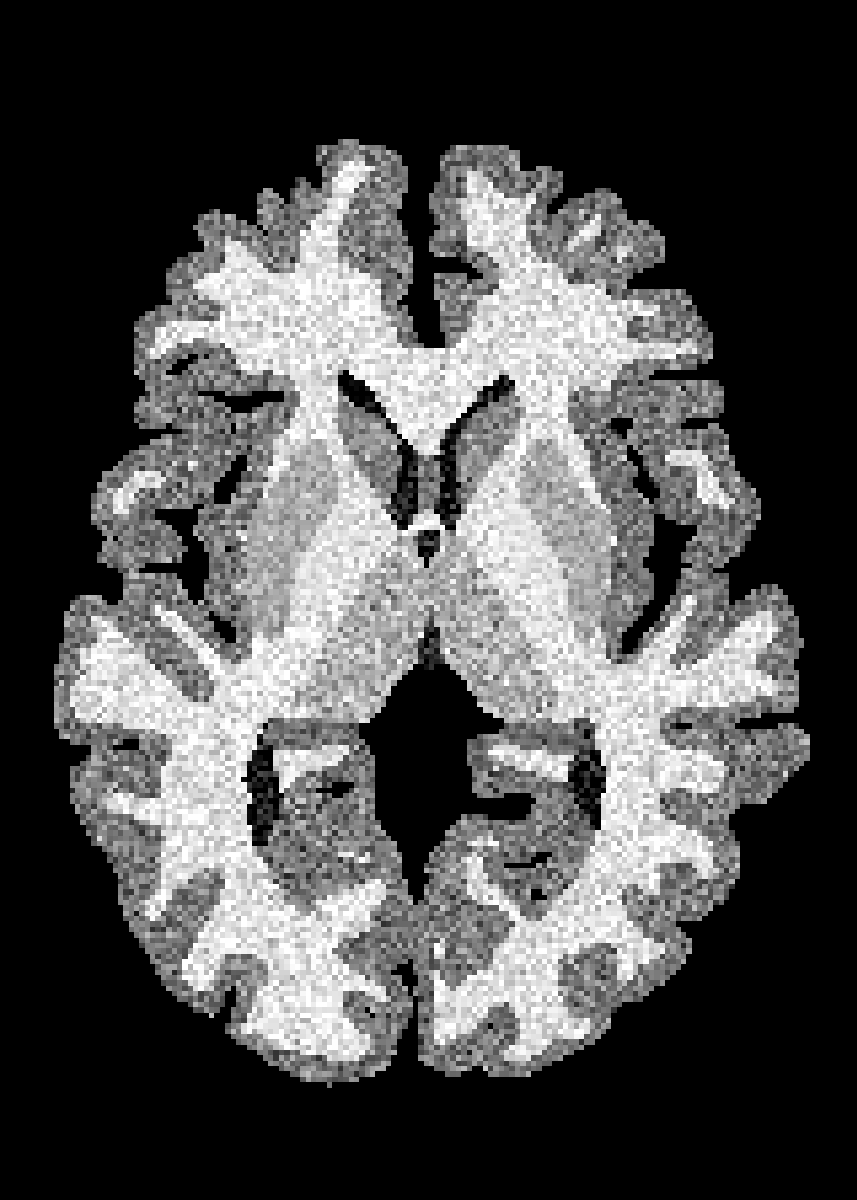

4.2 Registration to a 100 micron ex-vivo brain MRI volume

To showcase the efficacy of our method on real large scale images, we register a 250 in-vivo MRI image (Lüsebrink et al., 2017) to a 100 ex-vivo FLASH human brain volume (Edlow et al., 2019). This represents an inverse problem with more than 11.2B optimizable parameters (compared to 20M for clinical datasets), or 44.8GB of GPU memory. The entire problem does not fit on most GPUs, necessitating distributed multimodal registration. We optimize a composite transform - affine followed by a diffeomorphic mapping; details can be found in Section E.1. Multimodal deformable registration took 58 seconds on 8 NVIDIA A6000 GPUs, which is unprecedented at this resolution. Fig. 6 shows qualitative results, highlighting the ability to register highly detailed structures such as cerebellar white matter; these structures are not visible at macroscopic scales. The resultant advantages of performing registration at this scale can allow researchers to characterize the neuroanatomy at microscopic resolutions and allow morphometric analysis of cortical layers and subcortical nuclei among other structures.